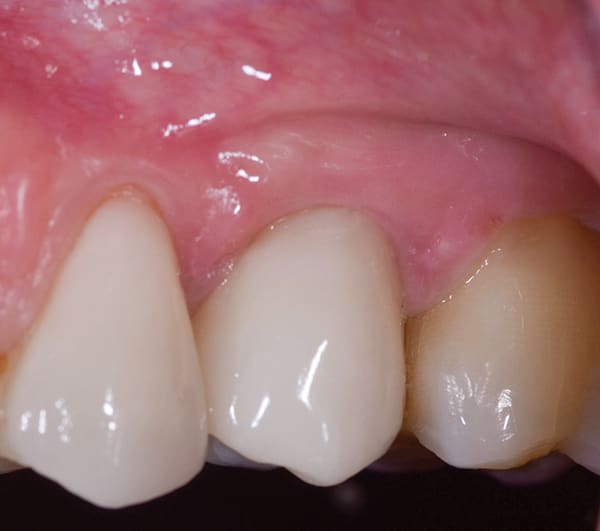

Missing Facial Plate

Screw-retained restorations are preferable to cementation for reasons of retrievability and biological complications. Due to the anatomy of the anterior maxilla, angle correction is required for the prosthetic table to be in the correct position to allow screw retention in many cases. Angled abutments increase cost and take up vertical prosthetic space. Using a 24° dual-axis implant (Co-Axis) allows the implant to engage the palatal bone and achieve primary stability regardless of the missing buccal plate. The implant was tightened to 50 Ncm, and the facial plate was grafted with a combination of allograft and xenograft, maintaining tissue contours.